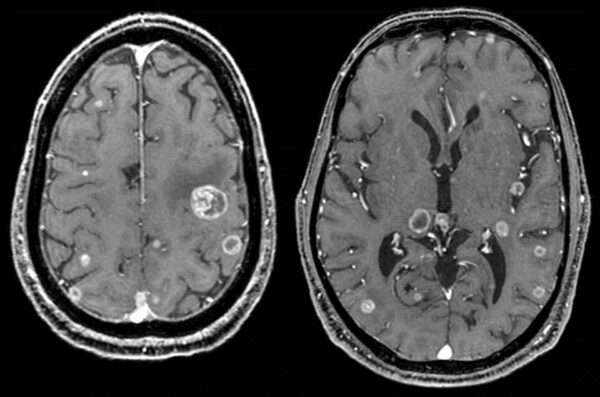

Los tumores metastásicos intracraneales pueden presentarse de manera similar a otros tipos de neoplasias cerebrales, con síntomas que incluyen un aumento de la presión intracraneal, alteraciones focales o difusas en la función cerebral, o bien ambos tipos de manifestaciones. En ocasiones, cuando un paciente presenta una sola lesión cerebral, el diagnóstico de metástasis cerebral solo se confirma mediante un examen histopatológico, es decir, al analizar el tejido tumoral en el laboratorio.

En otros casos, la metástasis cerebral puede ser evidente en pacientes con una enfermedad metastásica generalizada, o puede aparecer de forma aislada en el cerebro durante el tratamiento de un tumor primario en otra parte del cuerpo. De los diversos tipos de cáncer que pueden originar metástasis en el cerebro, los más comunes incluyen el carcinoma de pulmón, el carcinoma de mama, los tumores renales, el melanoma de piel y los cánceres gastrointestinales. Estos tumores metastásicos se localizan principalmente en la región supratentorial, que es la parte superior del cerebro, por encima de la tienda del cerebelo.

Para evaluar a los pacientes con sospecha de tumores metastásicos intracraneales, se emplean una serie de estudios laboratoriales y radiológicos. Las herramientas más utilizadas incluyen la resonancia magnética (RM) y la tomografía computarizada (TC), realizadas tanto con como sin contraste. Estas pruebas de imágenes ayudan a visualizar la extensión y localización de las lesiones tumorales en el cerebro. En casos específicos, como cuando se sospecha de meningitis carcinomatosa (infección de las membranas que rodean el cerebro y la médula espinal debido a metástasis), puede ser necesario realizar una punción lumbar para obtener muestras del líquido cefalorraquídeo.